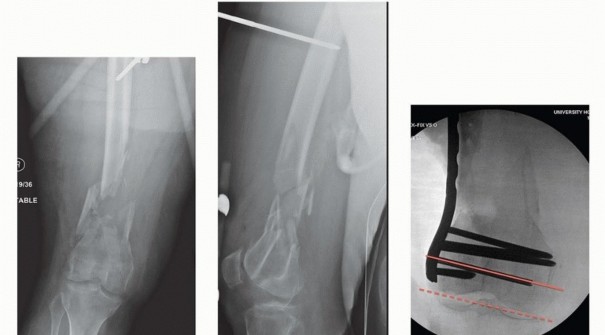

### FIG 9 • Critically ill elderly polytrauma Jehovah's witness patient with left C1 distal femur fracture. A,B. Initial injury AP and lateral views. C,D. Due to extremely low hematocrit, external fixation was the only surgical option allowed to minimize blood loss. Radiographs in bridging external fixation. The AP shows excellent alignment but the lateral shows the expected extension deformity secondary to pull of gastrocsoleus complex. E,F. After 5 weeks in an external fixator, AP and lateral radiographs show callus formation (red arrows). Patient is now cleared for definitive surgical intervention. Antegrade intramedullary nailing has been described and can be used for distal fractures with a large enough distal segment to allow for two locking screws. Malalignment has been a problem, as has adequate fixation. 4, 8 Retrograde intramedullary nailing can be used in the following cases ( FIG 10): All extra-articular type A fractures greater than 4 cm from the joint. This minimal length of the distal femur allows for multiplanar interlocking in the distal fragment. Type C1 or C2 fractures where the articular fracture can be anatomically reduced closed or with limited exposure. Percutaneous screws are used for the articular injury. Periprosthetic fractures around a total knee arthroplasty with an “open box” femoral component Most surgeons prefer to use a long nail, but short supracondylar nails are available as well. Multiple-hole short supracondylar nails have fallen out of favor. Plate fixation ORIF with plates can be used for all types A and C fractures but is ideal for the following injuries: Very distal type A fractures within 4 cm of the knee joint All articular type C fractures, but always for C3 types Periprosthetic fractures about a “closed box” femoral component of a total knee arthroplasty The partial articular type B1 or B2 if an antiglide plate is needed Plate options (preferred to least preferred; fixed-angle devices preferred) Fixed-angle locking plates (percutaneous jigs are advantageous and allow for minimally invasive techniques) Variable-angle (polyaxial) locking plates—allow for “fixed variable locking” within a defined range. It is useful for distal fractures and allows for increased screw 473 trajectories to gain additional locked fixation in short segments, which may not be feasible with fixed-angle trajectory plates ( FIG 11).

### FIG 10 • A,B. AP and lateral radiographs of an elderly patient with multiple comorbidities with an extra-articular distal femur fracture (AO type A; an incomplete intercondylar split— red dashed arrow). C,D. Postoperative radiographs showing stabilization with retrograde intramedullary nail. E,F. One-year postoperative radiographs showing a healed fracture with some subsidence of the metaphyseal region and mild protrusion of hardware through the notch. Ninety-five-degree condylar screw Ninety-five-degree blade plate Nonlocking plates with or without medial support (medial plate or external fixation) Limited internal fixation Limited fixation with screws only can be used for partial articular type B, especially type B3. The amount of open reduction required depends on the adequacy of closed reduction techniques and obtaining an anatomic reduction of the joint surface. Headless screws are useful for type B3 fractures in which the screws have to penetrate the joint surface ( FIG 12). Countersinking the screw heads can also be performed. Biomechanics of fixation: implant considerations There has been concern that the newer locking plate constructs are too stiff, resulting in inconsistent and asymmetric callus formation. 9 Some clinical evidence show less callus formation with stainless steel plates versus titanium plates. 9 Conversely, a biomechanical study has not shown a significant difference mechanically between constructs of stainless steel LISS plates with bicortical screws or titanium LISS plate with unicortical screws.1 474